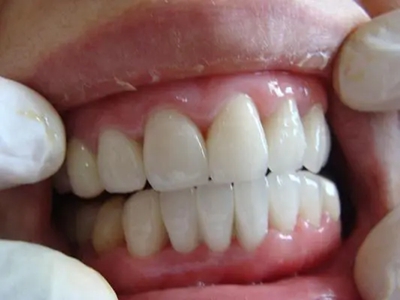

牙齿

小坑 · 缺损

牙釉质发育不全牙齿缺损有小坑图

重度牙釉质发育不全导致牙釉质表面呈棕褐色、棕黄色,其上有条状、窝状凹陷,并出现牙齿缺损,导致咬合关系破坏,也会出现对刺激敏感、疼痛等自觉症状。